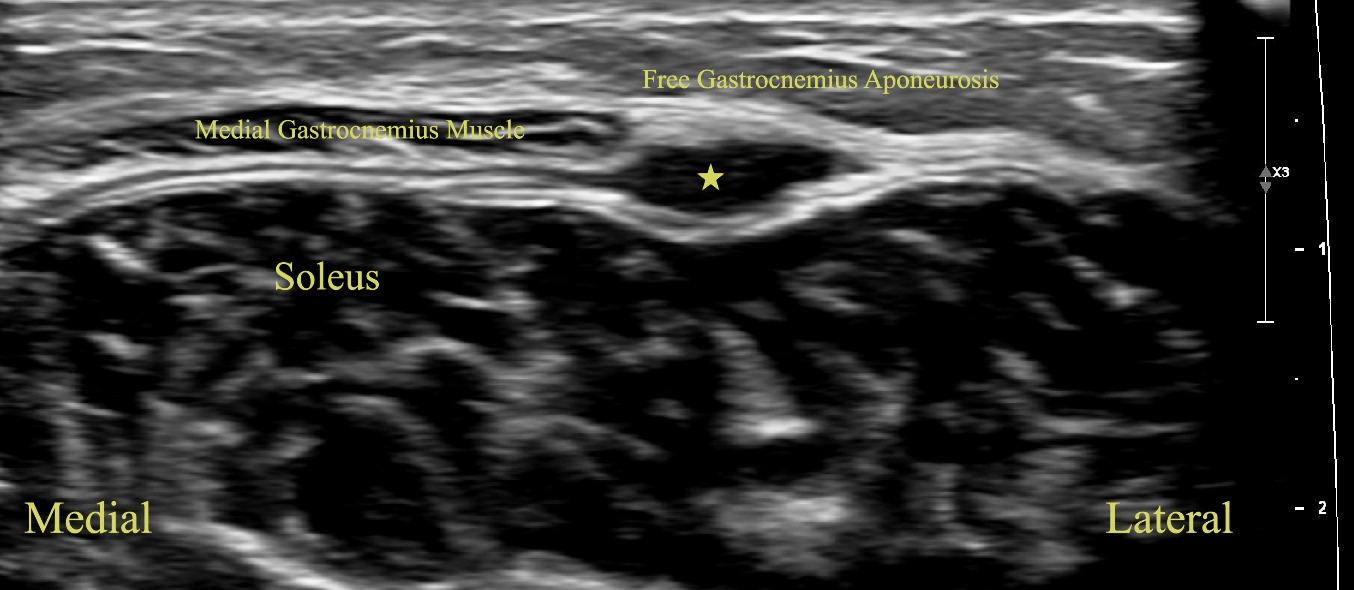

Short Axis view of Left Medial Gastrocnemius Soleus Aponeurosis with Free Gastrocnemius Aponeurosis Hematoma (Star)

Short Axis View of Left Medial Gastrocnemius Soleus Aponeurosis with Free Gastrocnemius Aponeurosis Hematoma